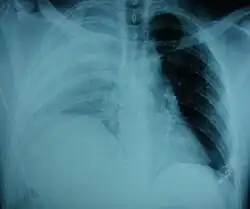

| An X-ray showing a raised diaphragm on the right[1] | |

Physical examinations are not accurate, as there is usually no specific physical sign that can be used to diagnose this condition.[3] Thoracoscopic and laparoscopic methods can be accurate.[12] Chest X-ray is known to be unreliable in diagnosing diaphragmatic rupture;[4] it has low sensitivity and specificity for the injury.[5] Often another injury such as pulmonary contusion masks the injury on the X-ray film.[6] Half the time, initial X-rays are normal; in most of those that are not, hemothorax or pneumothorax is present.[4] A nasogastric tube from the stomach may appear on the film in the chest cavity; this sign is pathognomonic for diaphragmatic rupture, but it is rare.[4] The X-ray is better able to detect the injury when taken from the back with the person upright, but this is not usually possible because the person is usually not stable enough; thus it is usually taken from the front with the person lying supine.[5] Positive pressure ventilation helps keep the abdominal organs from herniating into the chest cavity, but this also can prevent the injury from being discovered on an X-ray.[4]